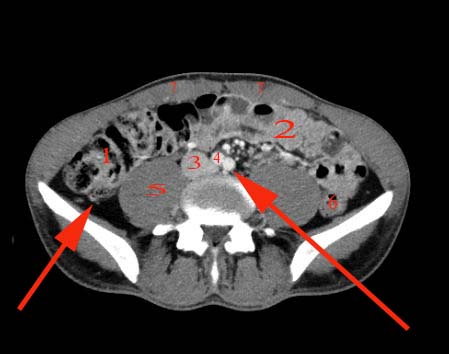

Abdomen axial IQ Test